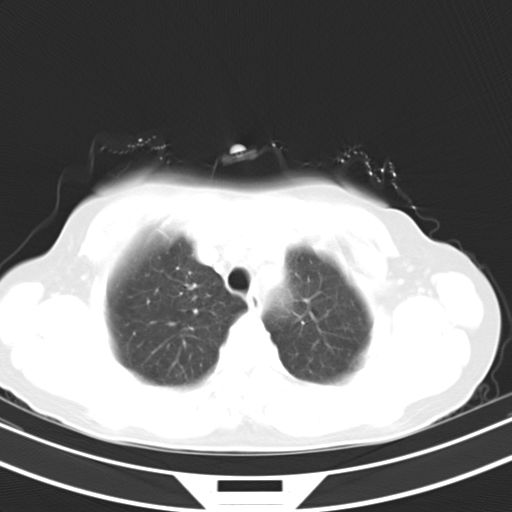

女,47岁,咳嗽胸痛一个星期,我们考虑肺结核,左下肺病灶肿瘤像不像,请高手指点。急。

炎性灶;【1楔状实变影,有支气管气象,2近端纹理影增重】

右肺为炎性改变,左肺病灶影像所见1、楔状实变影,边缘呈刀切样,见支气管气象,2、近端纹理影增重。

并从一元化来解释,还是符合炎性病灶。建议抗炎后复查。

两肺病变考虑炎症可能性大。(左肺病变呈楔状实变影,有支气管气象,近端纹理影增重)。

考虑右肺上叶前段及左肺舌叶炎症,建议抗炎治疗后复查除外结核。

左肺舌叶病灶呈扇形分布,其内可见支气管影,胸膜面光滑,不支持肿瘤病变。